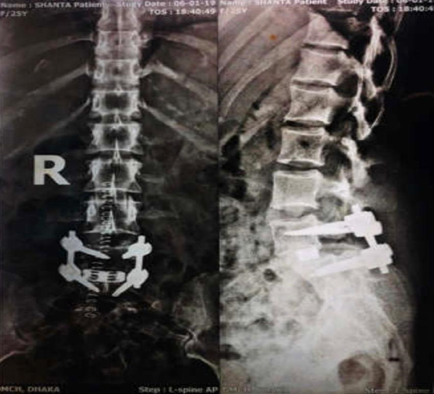

Figure 2 Patient no.7.a) Preoperative lateral view showing Grade 2 Spondylolisthesis at L5-S1 level. b) Preoperative MRI insagittal section. c) Xray at 6weeks followup; Inset shows immediate postop CT. d)Xray lateral view at 6 months followup.

Figure 4 Post-operative x ray of same patient.